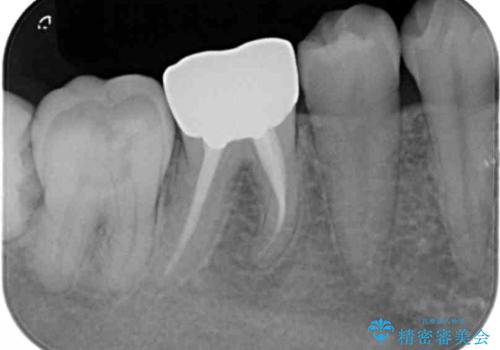

- 右下の奥歯に入れた銀歯を白くしたいとのことで来院されました。

根っこの治療がされていますが、症状もなくレントゲン画像で病変も確認できないため根管内には触れず被せ物のやり替えのみとなりました。